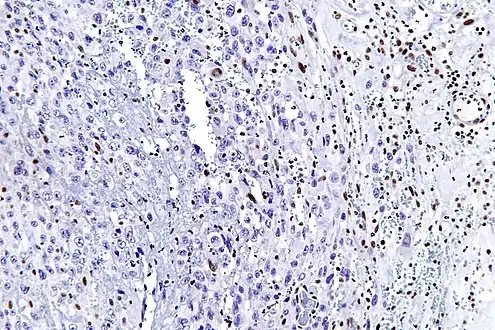

The most common genetic mutation (found in 80-90% of epithelioid sarcomas) is the inactivation of the SMARCB1 gene, or the loss of INI-1 function,[10][11] which is thought to be a major contributor to disease progression. Epithelioid sarcoma typically contains chromosome 22q11.2 mutations or deletions and 8q gains, particularly i(8) (>q10). Aberrations of 18q and 8q, as well as recurrent gains at 11q13, have also been observed.[12][13][14]

The SMARCB1 gene (also termed BAF47, INI1, or hSNF5) is located on chromosome 22q11.2[10] and codes for a member of the SWI/SNF chromatin remodeling complex. Loss of SMARCB1 function is the most common genetic mutation observed in epithelioid sarcoma, and this dysfunction is likely a major driver of disease progression. SMARCB1 is a core protein subunit of the 15 subunit SWI/SNF (or BAF) complex involved in regulating the nucleosome architecture of our genome[10] and has been shown to be a potent tumor suppressor gene,[11][15] meaning that its primary role is to control cell division and to even halt division under appropriate circumstances (i.e. signals to over-replicate). As this tumor suppressor is commonly inactivated in epithelioid sarcoma, cell division can fail to appropriately halt, resulting in unregulated cellular growth and the formation of cancer tumors. Several research teams are currently developing techniques to reverse this loss of genetic function characteristic of epithelioid sarcoma.[6]

Tissue biopsy is the diagnostic modality of choice. Due to a high incidence of lymph node involvement, a sentinel lymph node biopsy is often performed. A common characteristic of epithelioid sarcoma (observed in 80% of all cases) is the loss of function of the SMARCB1 gene (also termed BAF47, INI1, or hSNF5). Immunohistochemical staining of INI1 is available and can be used for the diagnosis of epithelioid sarcoma. MRI is the diagnostic modality of choice for imaging prior to biopsy and pathologic diagnosis, with the primary role being the determination of anatomic boundaries.

High mag. (SMARCB1)